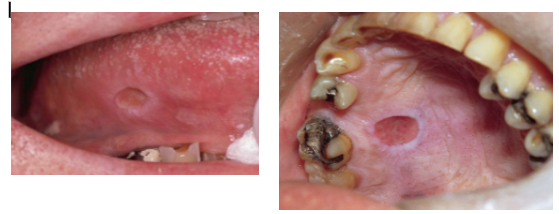

Minor aphthous ulcers

Very painful; pain dipropionate to size

Seen in anterior regions of mouth

Major aphthous ulcer

Larger than minor aphthae

Last for longer duration per episode

Take 2-6 weeks to heal

May cause scarring